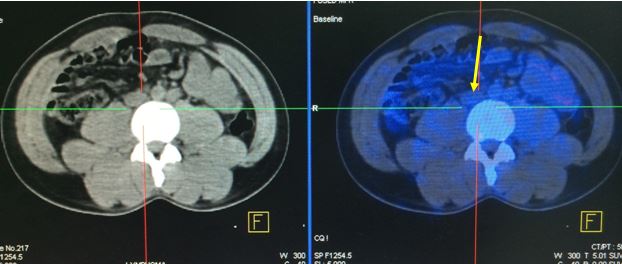

Trên CT ổ bụng có tổn thương hạch cạnh động mạch chủ bụng 1,3cm, nghi ngờ bệnh chưa đáp ứng hoàn toàn hoặc bệnh tiến triển. Bệnh nhân được vào viện chụp PET/CT kiểm tra.

Tổn thương hạch ổ bụng còn lại trên CT sau R- CHOP x 8.

Sau khi được chụp PET/CT, có điều đặc biệt ở bệnh nhân này là tổn thương hạch ổ bụng phát hiện trên CT lại hoàn toàn không tăng hấp thu FDG, mà bệnh nhân lại được phát hiện thêm một tổn thương tăng hấp thu FDG bất thường ở đầu xương ức. Các vị trí khác trong cơ thể không có tăng hấp thu FDG bất thường.

Tổn thương hạch ổ bụng hoàn toàn không hấp thu FDG.

Tổn thương đầu xương ức tăng hấp thu FDG( tổn thương này hoàn toàn không phát hiện được trên CT thường).